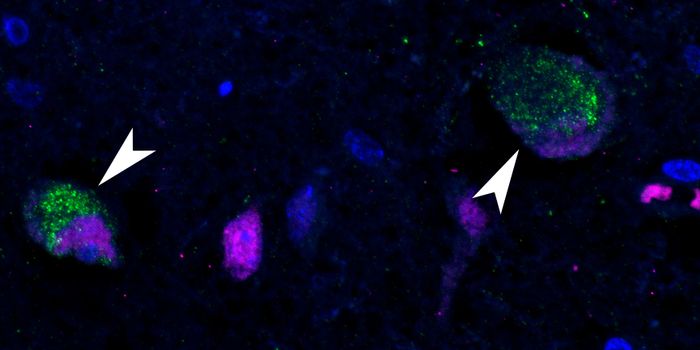

OCT 17, 2023Clinical & Molecular DXIn this photo, courtesy UC San Diego Health Sciences, regenerating neurons (yellow) can be seen along with non-regenerat ...